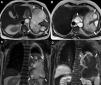

Axial T2-weighted MRI (A and B, respectively) show transdiaphragmatic lesion at the spleen level and multiloculated cystic lesion (arrows) with mediastinal extension at the level of esophageal hiatus. The presence of daughter vesicles in the cysts and the presence of relatively hypointense thick walls are typical features of the hydatid cyst. In the coronal T2-weighted (C) MR image, the cystic lesion (arrows) substantially fills the left hemithorax. The coronal image also reveals minimal pleural effusion. Postcontrast coronal T1-weighted (D) MR image reveals contrast enhancement (arrows) at the lesion's periphery. Moreover, the left lower lung is seen compressed by the cyst.

A 70-year-old man presented to clinic with short of breath and chest pain. MRI showed a giant cystic lesion compressing the spleen and left lung (Fig. 1). Because ofthe presence of multiloculated cystic lesion and daughter vesicles on MRI, hydatid cyst was considered. The diaphragmatic hydatid cyst was resected with video assisted thoracoscopic surgery. During surgery, there was no evidence of hydatid cyst involvement in the lung or spleen. No complication was observed in the postoperative period.